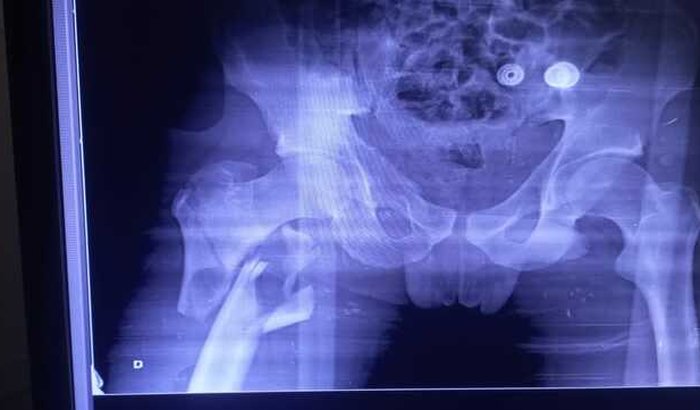

Oi, eu me chamo Marcos Adriane Poiate tenho 28 anos , moro em Morretes PR, bairro Mundo Novo do Saquarema. dia 19/01  Sofri um acidente na BR 277 km19 no acidente acabei fraturando o  fêmur, clavícula, trincou bacia e quebrou duas costelas , fiquei 15 dias no hospital onde passei por várias cirurgias  E agora estou acamado sem poder andar, estou fazendo essa vaquinha que no momento não tenho condições financeiras para comprar meus medicamentos que custam caro. Sua colaboração vai ser muito gratificante para esse momento difícil que eu estou passando que. Deus abençoe a todos que puderem me ajudar nesse momento.